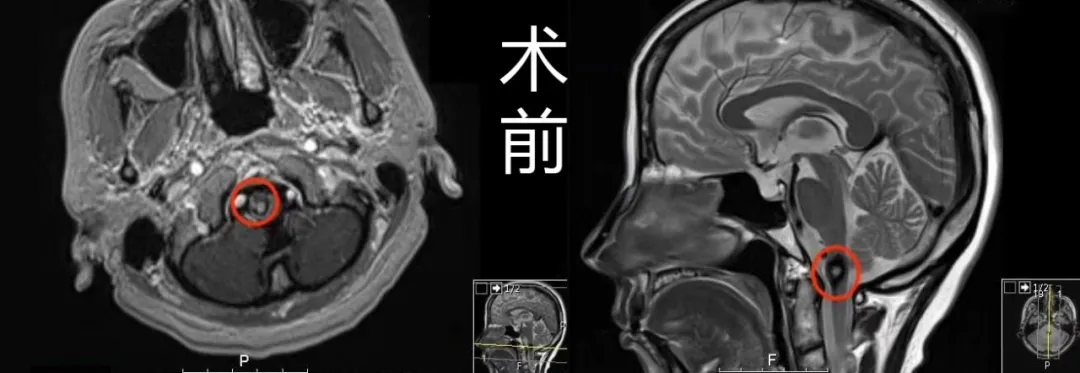

(术前术后MR对比)

术前MR:延颈髓偏右侧见一直径约1cm占位,周围见环状含铁血黄素低信号影环绕,提示海绵状血管瘤。